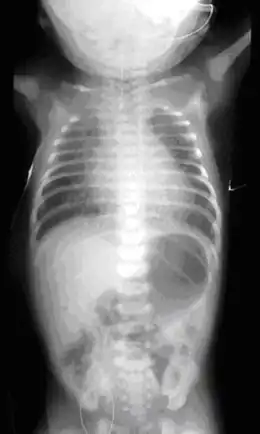

Slokdarmatresie

- Een slokdarmafsluiting.